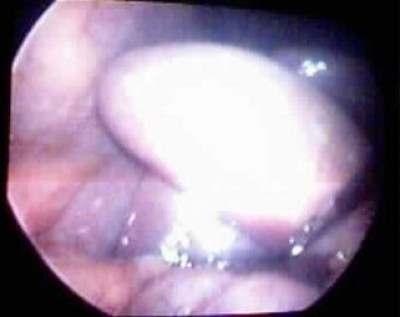

Vesícula muy atrófica

Post Image